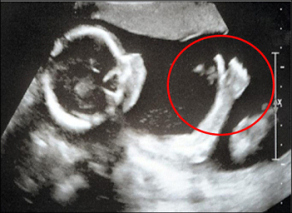

يقوم الجنين بحركات عديدة داخل رحم المرأة يصعب تحديدها، لكن شاءت الصدفة ان يقوم هذا الجنين بالتحرك اثناء افحص الطبي التي تجريه والدته. حيث اعلن جنين لامه في بريطانيا انه على ما يرام وذلك برفع ابهامه لأعلى، عندما قامت الام بعمل مسح ضوئي له (سونار) في المستشفى.

وذكرت صحيفة الديلي البريطانية ان ماري بوسويل (35 عاما) الحامل في شهرها الخامس، ذهبت للفحص الطبي وقامت بإجراء مسح ضوئي للجنين وعندما شاهدت صورته على الجهاز وهو يرفع ابهامه لاعلى لم تستطع التوقف عن الضحك وشاركتها امها ذلك والتي كانت بصحبتها. تقول ماري انه موقف طريف وتعتقد انه سيصبح حارس مرمى في ملاعب كرة القدم. يذكر أن ماري ستضطر الى اجراء فحص طبي آخر للجنين، لفحص العمود الفقري بحسب نصيحة الطبيب.